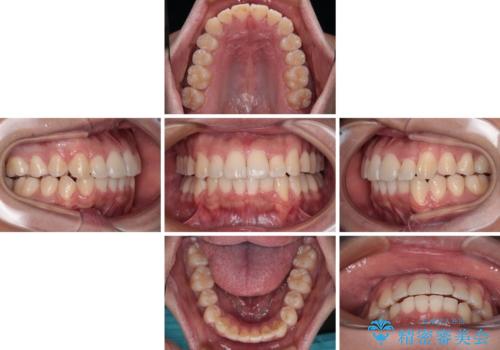

- 前歯のデコボコを治したいとのことで来院された患者様です。

上下顎ともに歯列全体の後方移動とIPR(歯と歯の間を削る)によってデコボコが解消するように設計し、インビザラインにより治療を行うこととしました。

下顎前歯は後戻りを起こしやすいため、舌側を細いワイヤーで固定し、マウスピース型リテーナーで保定を行うこととしました。